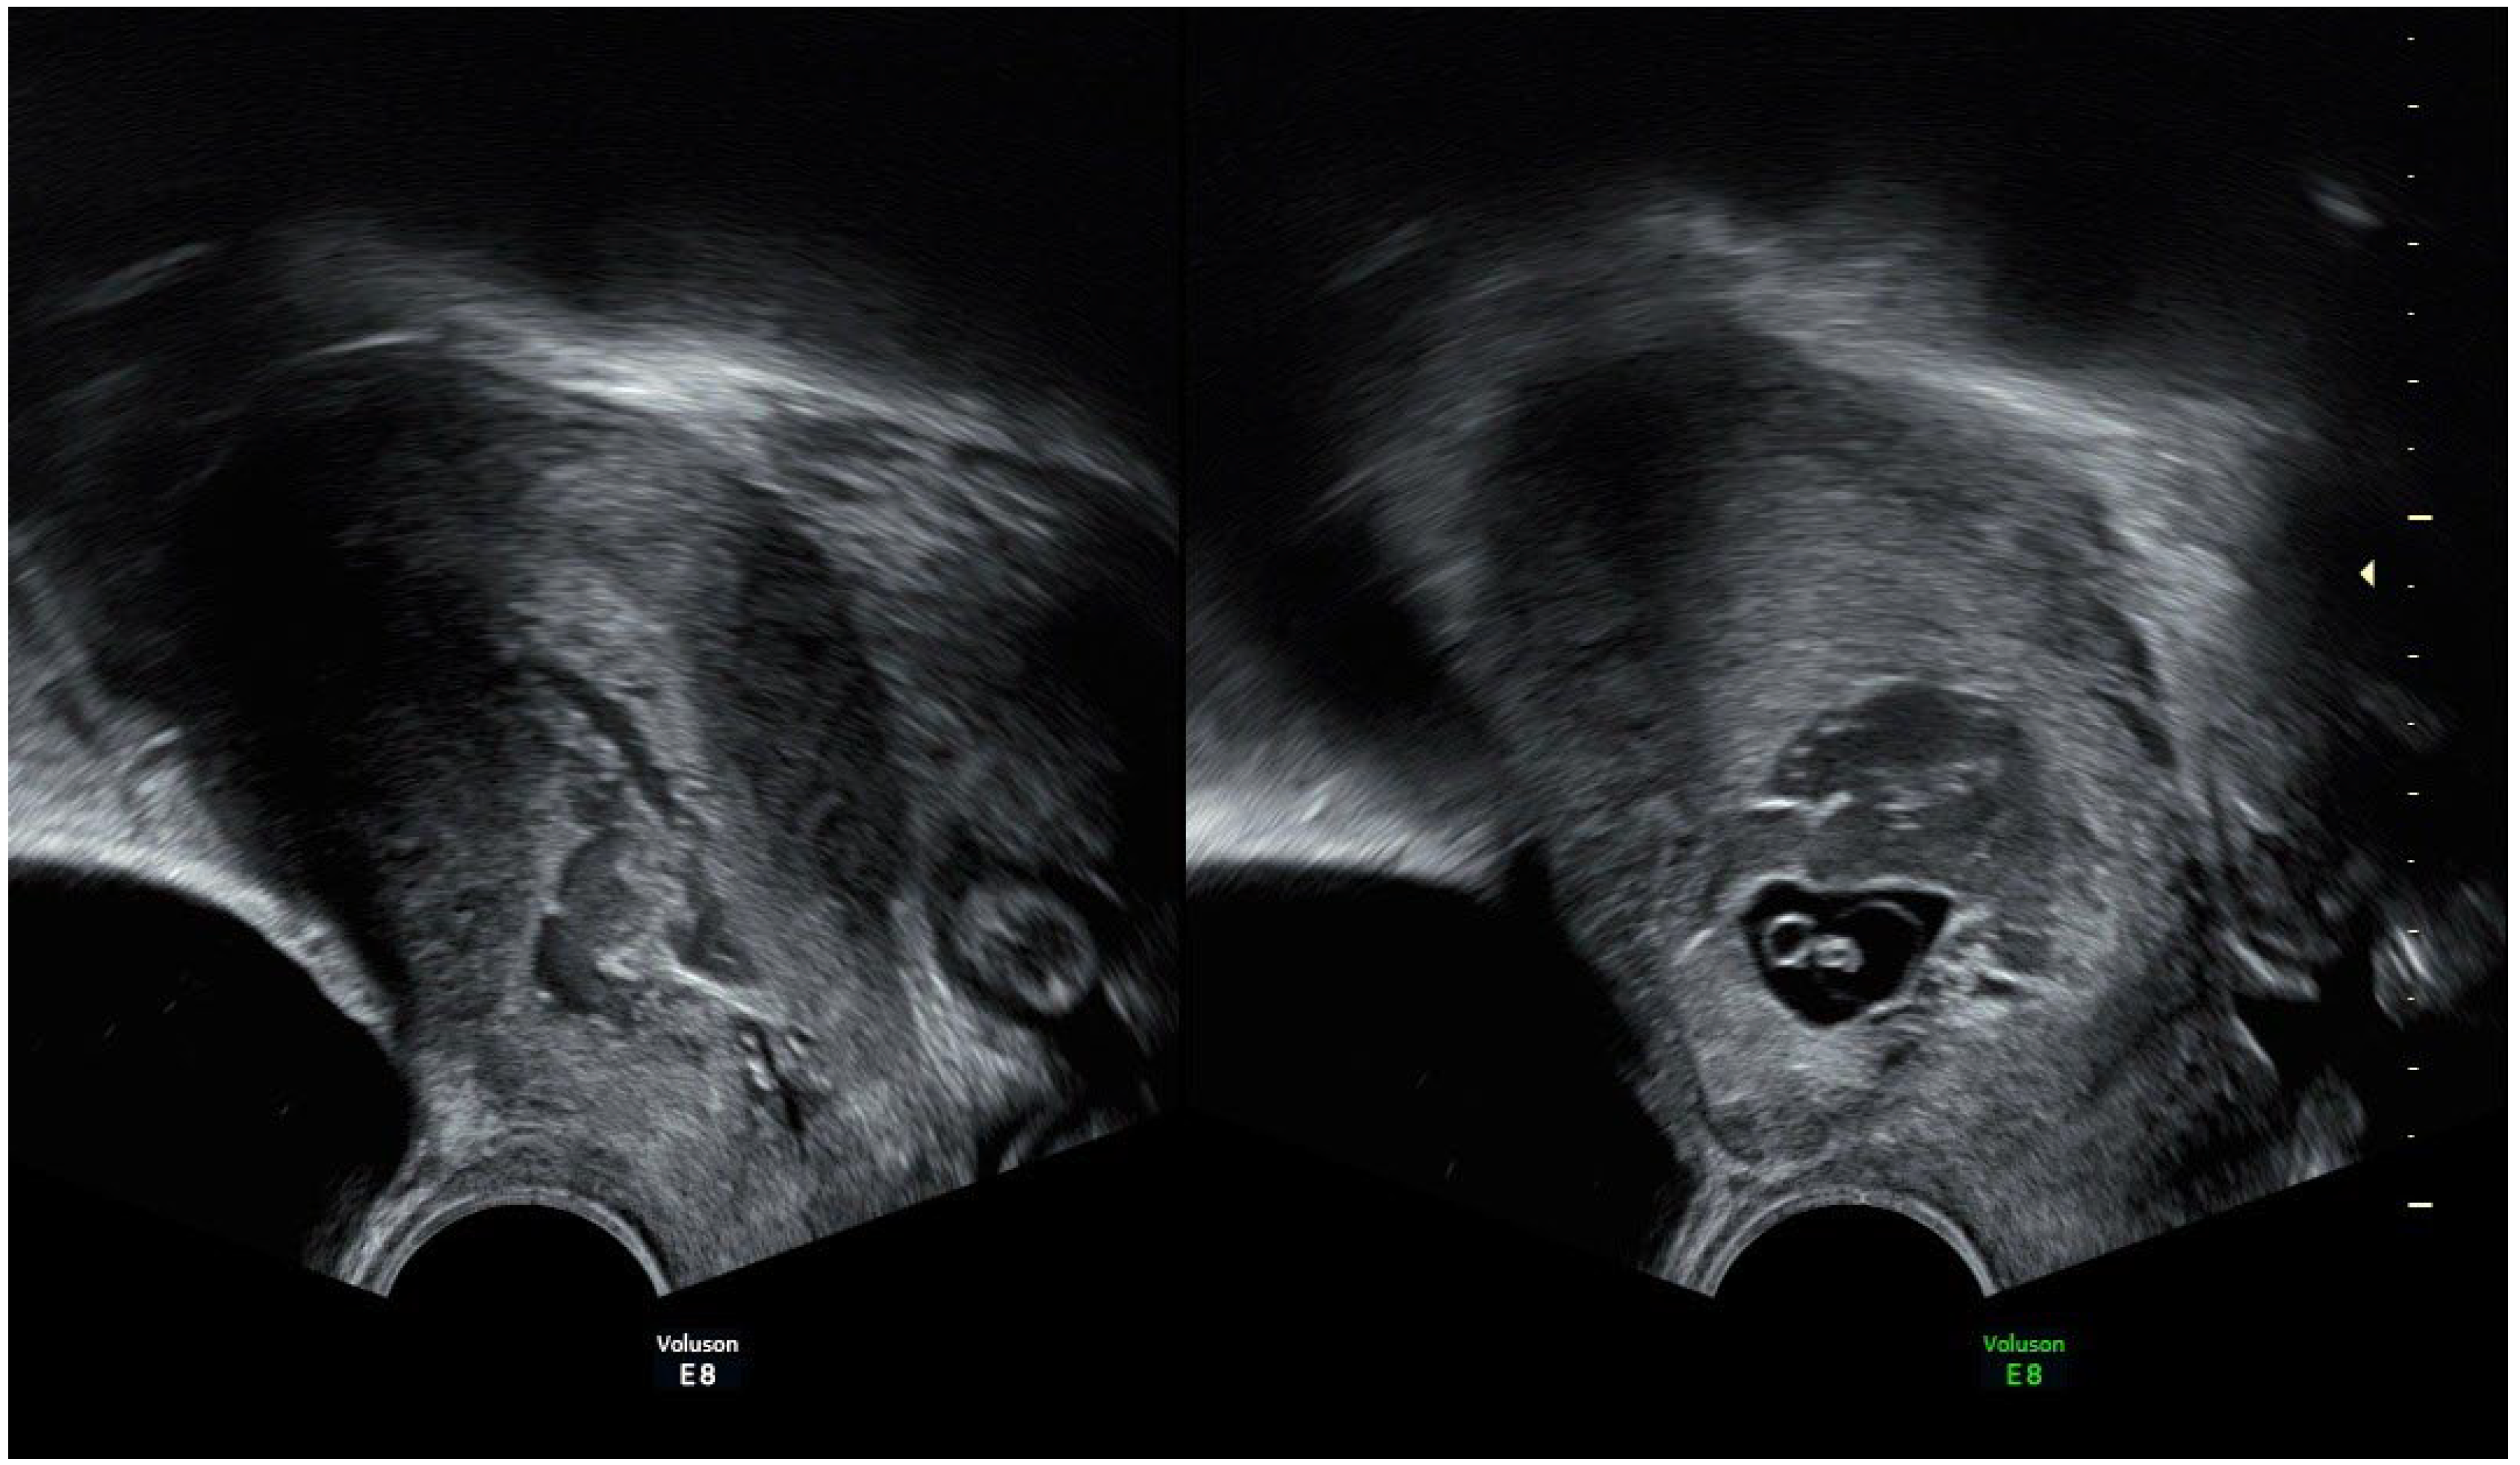

2. Case Presentation

| Characteristics | Case 1 | Case 2 |

| Age, years | 36 | 29 |

| Gestation | 3 | 3 |

| Parity | 1 | 2 |

| Previous cesarean sections | 1 | 2 |

| Gestational age, weeks | 8 | 6 |

| Symptoms | vaginal bleeding | lower abdominal pain |